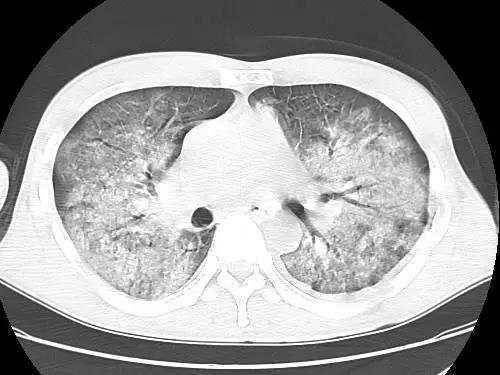

【影像读片】病毒性肺炎ct

图片尺寸2448x3264